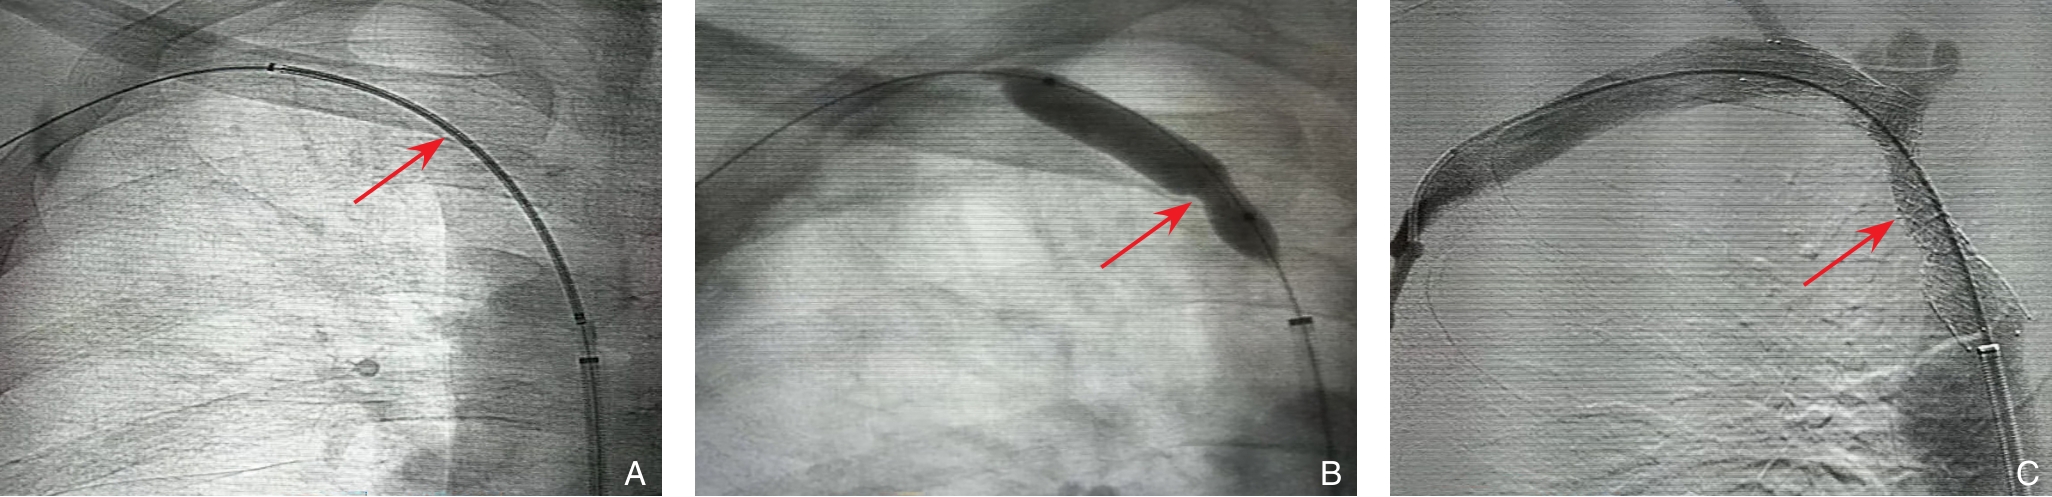

2025, 34(12):2577-2585. doi: 10.7659/j.issn.1005-6947.250429

摘要:背景与目的 胸主动脉腔内修复术(TEVAR)已成为治疗胸主动脉疾病的重要微创手段,但在近端锚定区位于Z0区的复杂主动脉弓部病变中,如何同期重建弓上分支血管仍是技术难点。Castor分支型主动脉覆膜支架可实现左颈总动脉(LCCA)的一体化重建,但其在Z0区应用通常需联合其他技术重建无名动脉(IA)。本研究旨在初步评估Castor分支型支架重建LCCA联合IA烟囱支架技术在Z0区TEVAR中的技术可行性及短期疗效。方法 回顾性分析2024年2月—2024年6月在中南大学湘雅二医院接受Castor分支型主动脉覆膜支架重建LCCA联合IA烟囱支架技术行Z0区TEVAR的主动脉疾病患者资料。收集并分析患者围手术期临床特征、手术相关参数及随访结果,主要观察指标包括技术成功率、围手术期并发症发生情况及弓上分支血管通畅率。左锁骨下动脉(LSA)是否同期重建依据术前影像学评估结果个体化决策。结果 共纳入6例患者,平均年龄51.5岁,男性5例。原发病包括主动脉夹层4例、主动脉弓部动脉瘤1例及穿透性主动脉溃疡1例。所有患者均成功完成手术,技术成功率为100%。其中3例同期行LSA血运重建。术后30 d内未发生死亡、脑卒中、截瘫、内漏、逆撕性A型主动脉夹层、支架移位及上肢缺血等严重并发症。中位随访13(11~15)个月,随访期间未出现主要不良心脑血管事件或支架相关并发症,影像学显示IA、LCCA及重建LSA通畅率均为100%。结论 在严格筛选的小样本患者中,Castor分支型主动脉覆膜支架重建LCCA联合IA烟囱支架技术用于Z0区TEVAR在技术上可行,且短期随访结果显示分支血管通畅率良好。但其安全性及远期疗效仍需通过更大样本量及长期随访研究进一步验证。